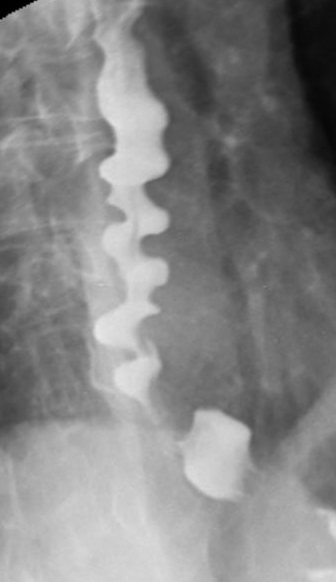

바륨 삼킴 X선 촬영에서 "코르크 마개 식도" 또는 "묵주 식도" 모양과 같은 몇 가지 방사선학적 소견이 광범위식도연축을 시사하지만, 이러한 소견은 광범위식도연축에만 특유한 것은 아니다.[1]

4. 1. 바륨 삼킴 검사